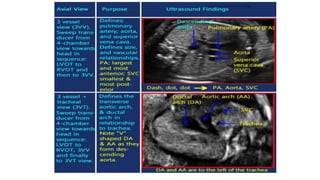

• #22 The three-vessel view. In this view, one can identify the three vessels from left to right (A) or anterior to posterior (B) as pulmonary artery (PA), aorta (A) and superior vena cava (V). The sizes of the pulmonary artery and aorta can be compared with the PA slightly larger than the aorta